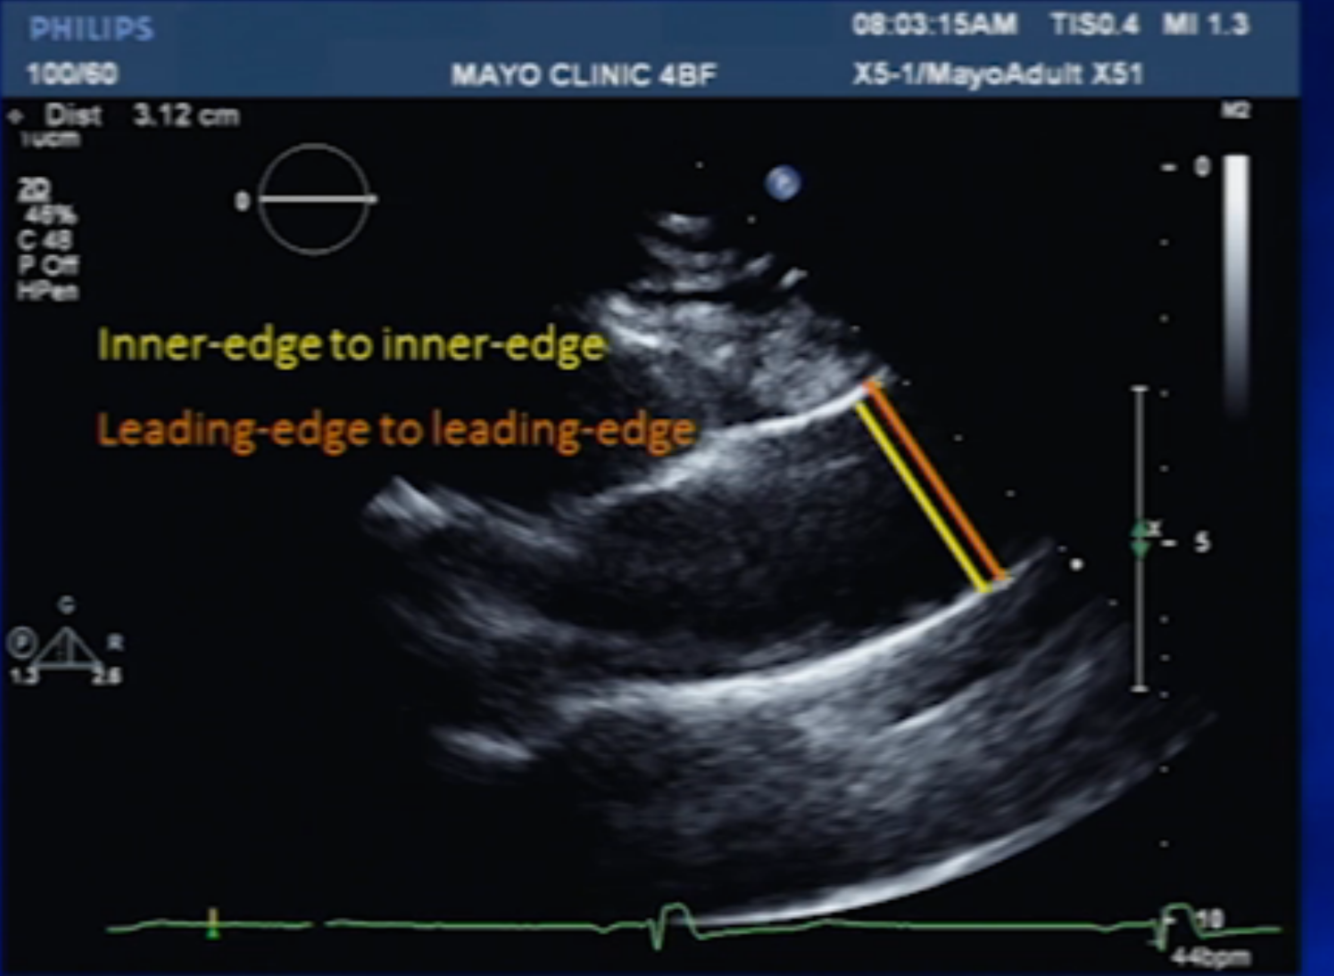

how do you measure Aortic root?

leading edge (outside edge) to leading edge at end DIASTOLE